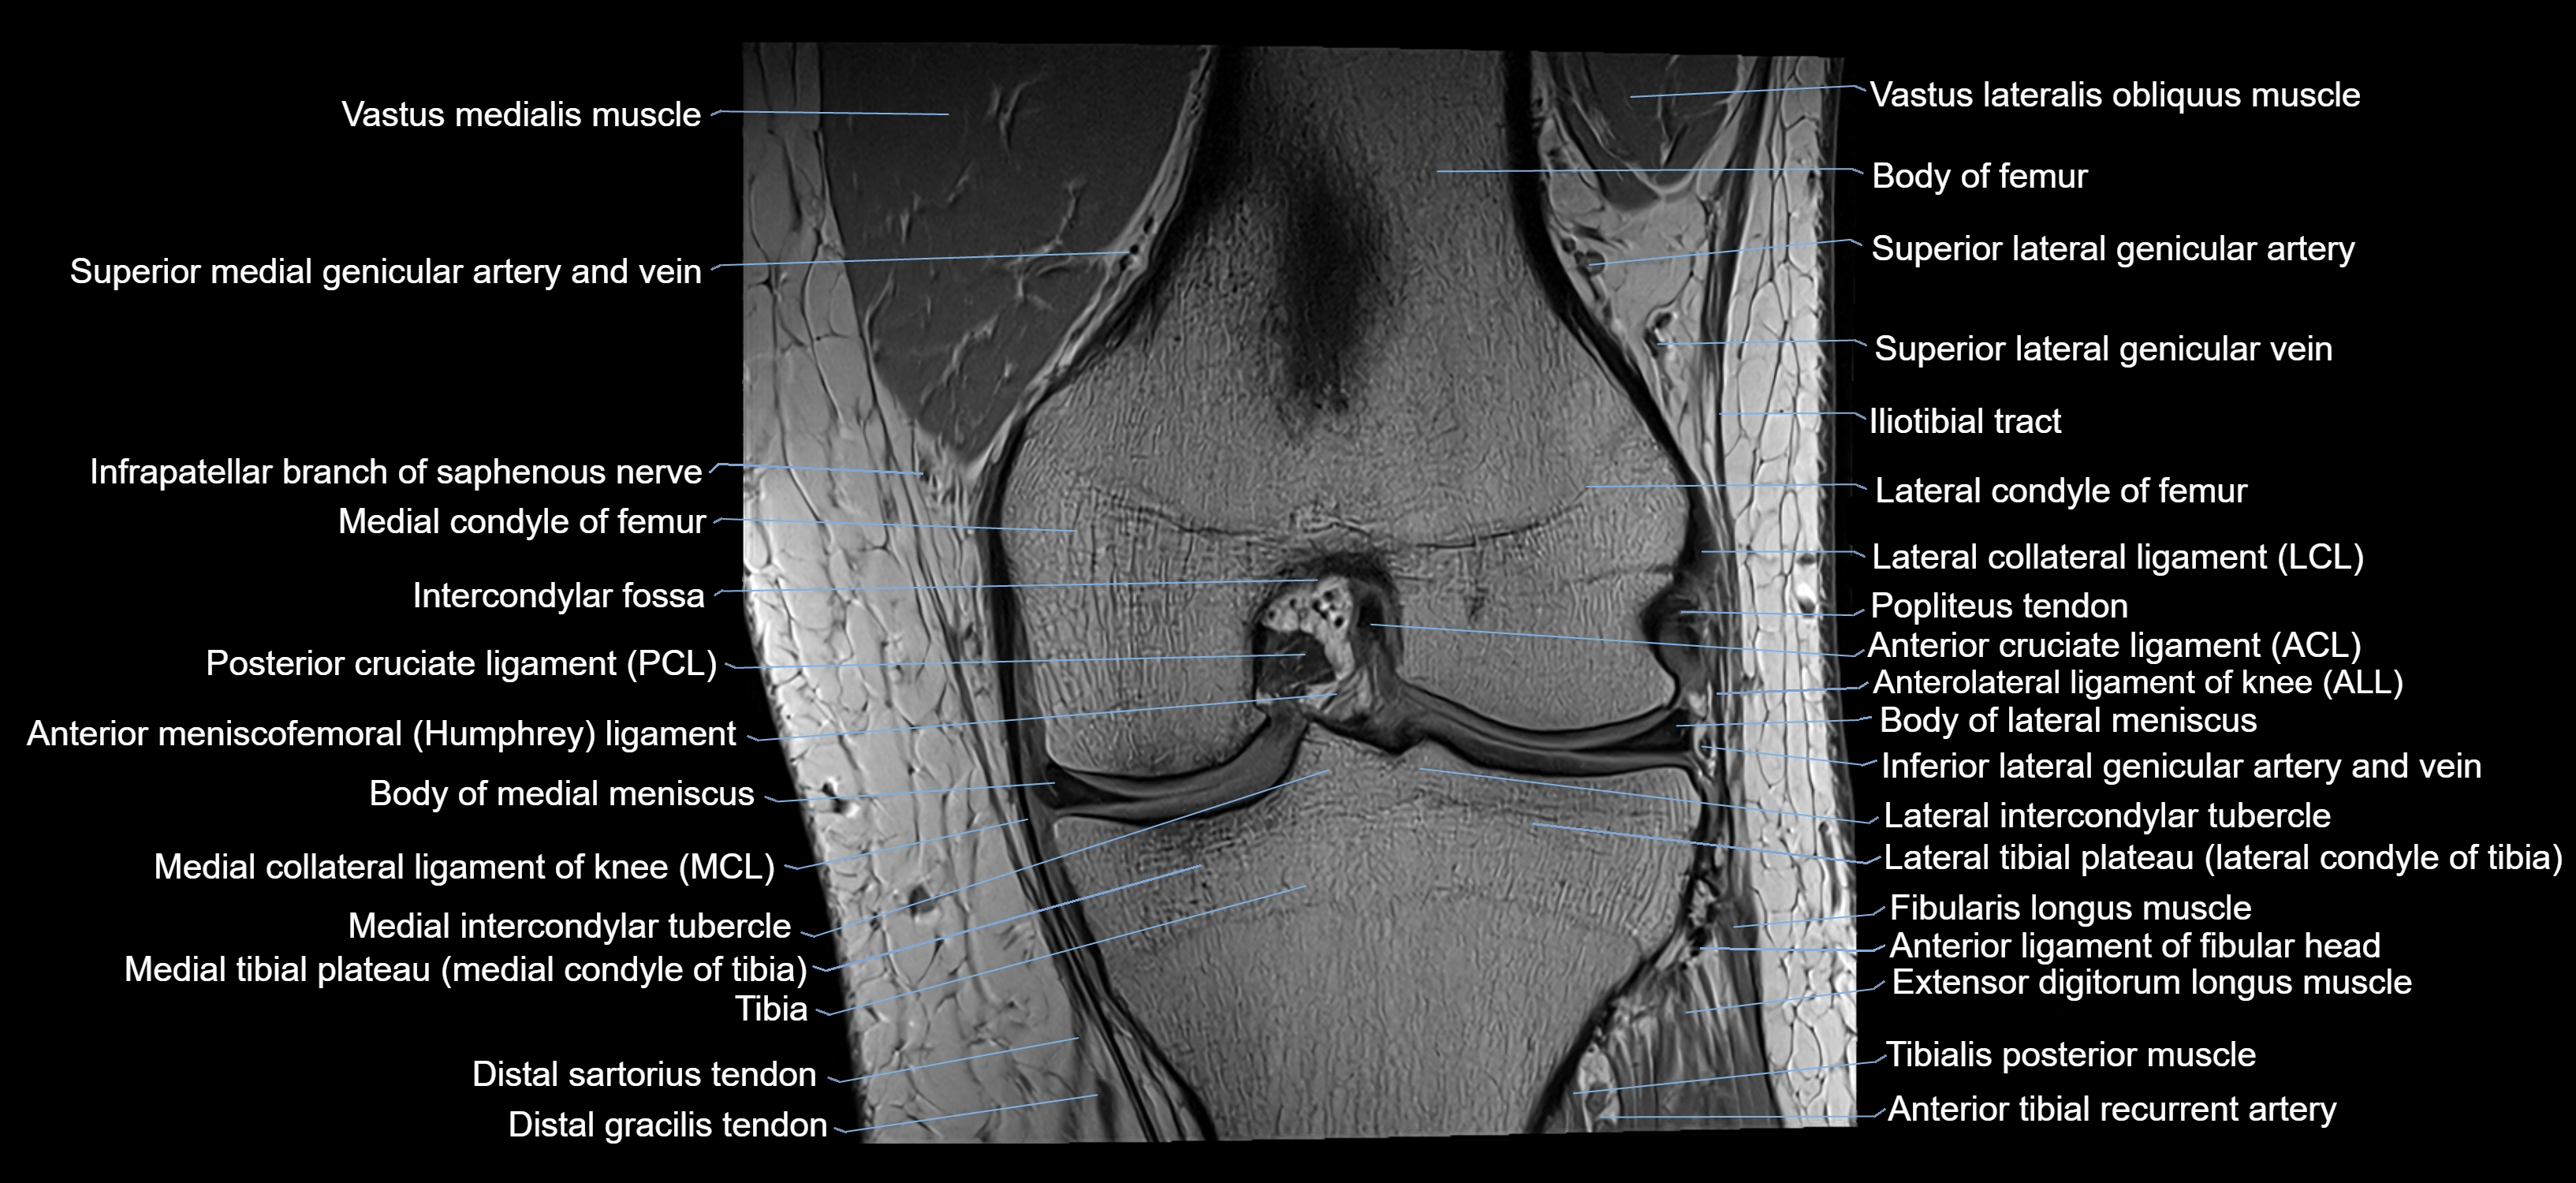

- Anterior cruciate ligament

- Anterior ligament of fibular head

- Anterior meniscofemoral ligament

- Anterolateral ligament of knee

- Body of lateral meniscus

- Body of medial meniscus

- Gracilis tendon (Distal)

- Infrapatellar branch of saphenous nerve

- Intercondylar fossa

- Lateral collateral ligament

- Lateral condyle of femur

- Lateral condyle of tibia

- Lateral epicondyle of femur

- Lateral intercondylar tubercle

- Lateral meniscus

- Lateral tibial plateau

- Medial collateral ligament

- Medial condyle of femur

- Medial condyle of tibia

- Medial intercondylar tubercle

- Medial tibial plateau

- Popliteus tendon

- Posterior cruciate ligament

- Sartorius tendon (Distal)

- Superior lateral genicular artery

- Superior lateral genicular vein

- Tibia

- Vastus Lateralis Obliquus Muscle

- Vastus lateralis muscle

- Vastus medialis muscle